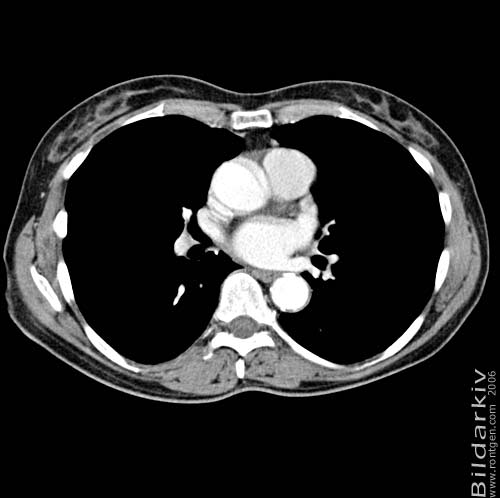

Snitt över thorax med kontrast. Sk. mediastinum-fönstersättning.

Mediastinum